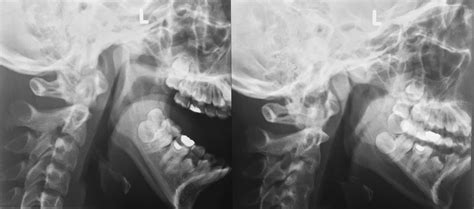

Reconstruction of a Severe Upper Jaw Defect For Dental Implants

Reconstruction of a Severe Upper Jaw Defect For Dental Implants ...